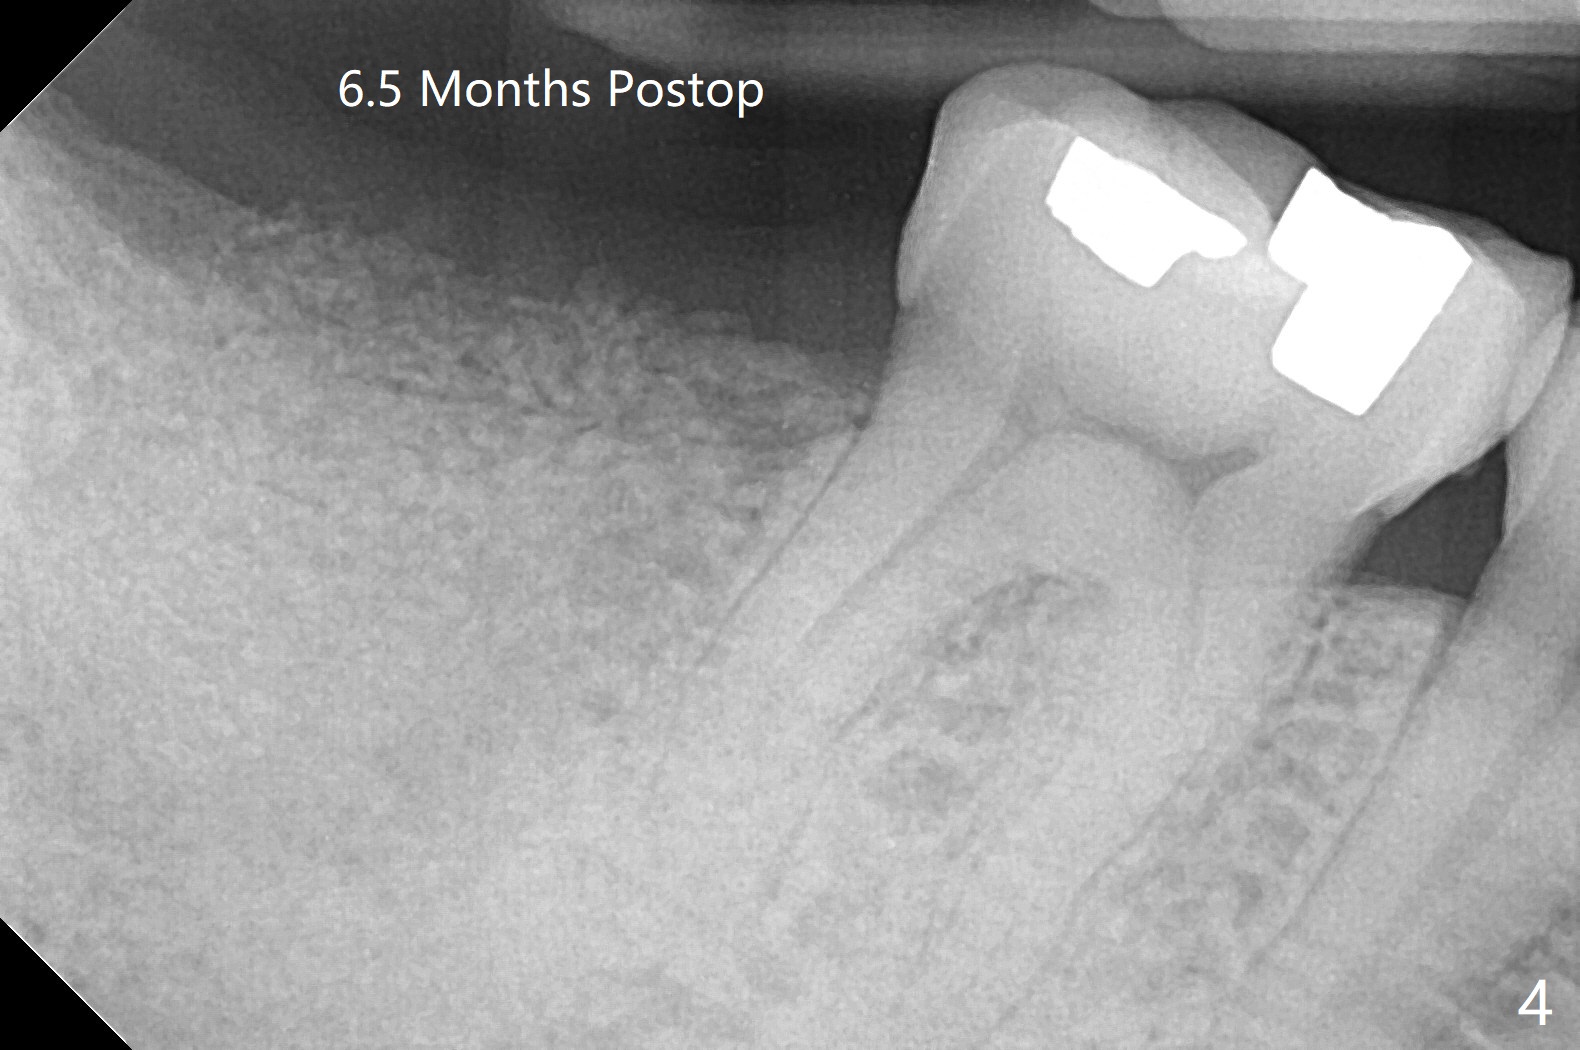

After immediate implant at #3, the tooth #31 with distal root fracture (Fig.1 *) and being close to the Inferior Alveolar Canal (red dashed line) is extracted for socket preservation (Fig.2 yellow dashed line). Although no PRF membrane is used to cover the socket, allograft is mixed with PRF liquid. A piece of 6-month membrane is used instead. The bone density is average 1000 units (Fig.3) and the ridge height is maintained 6 months postop (Fig.4). In fact the bone density of the grafted bone is low as compared to that of the native one.